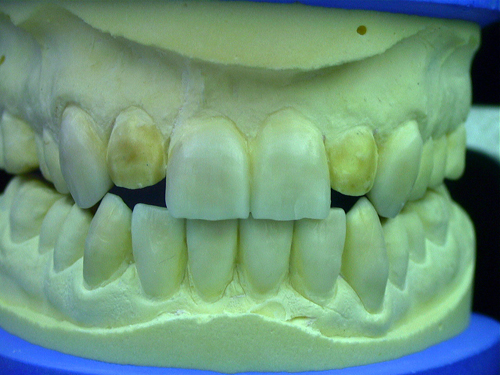

ABSTRACT El Bruxismo es una entidad patológica en la que concurren diferentes factores. Entre ellos el stress que conlleva consigo la vida moderna, constituye el Factor Predisponente sobre el que se ha abundado en innumerables tratamientos de tipo general, actuando sobre la psiquis y el comportamiento del individuo, ya sea con fármacos o bien mediante medios psicológicos. Sin embargo, como tantos desequilibrios provocados por el stress, confluyen siempre con un Factor Desencadenante, que en el caso del Bruxismo se encuentra en las desarmonías entre los componentes varios del Sistema Estomatognático. DESARROLLO Paciente varón, de 43 años, constitución atlética. A la inspección se observan desgastes oclusales que alcanzan la calidad de Facetas Parafuncionales, con dentina expuesta y empastes totalmente gastados y evidentes signos de falta de Disclusión Canina de ambos lados. Sobre dicho montaje se realiza un Encerado Progresivo de Diagnóstico, aportando en el mismo los elementos necesarios para obtener todos los principios básicos de una Oclusión Orgánica. FIG. 6 a 24 Una vez aprobado el fisiologismo de la oclusión en el articulador, se reproducen modelos de yeso con la nueva situación, y se estampa un SET UP en cada maxilar. FIG. 25/26 Procedemos entonces al tallado de las piezas correspondientes a la Guía Anterior, y rebasamos los estampados, creando en boca una nueva situación desoclusiva, que permanece en boca durante los pocos días que transcurren entre la primera y segunda visita de trabajo. FIG. 27/33 Ya abordando en esta segunda visita los sectores posteriores, tanto superiores como inferiores, tallamos siempre de manera supragingival, destacando la importancia vital de la forma obtenida en las provisionales, a las que abrimos plenamente las troneras para lograr una correcta higiene. FIG.34 a 43 FIG. 44 a 52 Efectuados los colados en oro y probados en boca, en el laboratorio se confecciona el bizcochado de la nueva Guía Anterior, la que puede o no copiarse de la Guía Anterior provisional, mediante la técnica denominada Trayectoria Funcionalmente Generada, que consiste en realizar en la platina del articulador un registro estereográfico sobre acrílico Duralay en polimerización. FIG. 57/58 Ajustados todos los detalles mediante esta técnica, se instala en boca en forma Provisional y se deja funcionando una semana o dos, al cabo de las cuales se chequean las disclusiones , los ajustes, la eficacia masticatoria, la carencia de sintomatología articular y muscular. FIG.59 a 63 PIE DE FOTO FIG.9 OBTENCIÓN DE LA GUÍA ANTERIOR FIG.10 Y 11 PITOMBOS. ALINEAC. TRIDIMENSIONAL FIG.12 PITOMBOS. DISCLUSIÓN DER. FIG.13 PITOMBOS. DISCLUSIÓN IZQ. FIG.14 WILSON INF. FIG.15 WILSON SUP. FIG.16 BOCA DE PEZ INF. FIG.17 BOCA DE PEZ SUP. FIG.18 VISTA OCLUSAL FIG.19 O.R.C. FIG.20 DISCLUSIÓN DERECHA FIG.21 CRESTAS TRIANG. INT. FIG.22 CRESTAS TRIANG. INT. FIG.23 CRESTAS TRIANG. INT. FIG 24 CRESTAS TRIANG. INT. FIG.59 DISCLUSIÓN IZQ. FIG.60 DISCLUSION IZQ. FIG.61 DISCLUSIÓN DER. FIG.62 DISCLUSION DER. FIG. 63 AJUSTE PERIFÉRICO

Se nos hace evidente la necesidad de proceder a rehabilitar todo el sistema, y se programa el correspondiente estudio oclusal, mediante un montaje en articulador semiajustable, el que se realiza luego de dos semanas de uso de una Férula de Desprogramación.